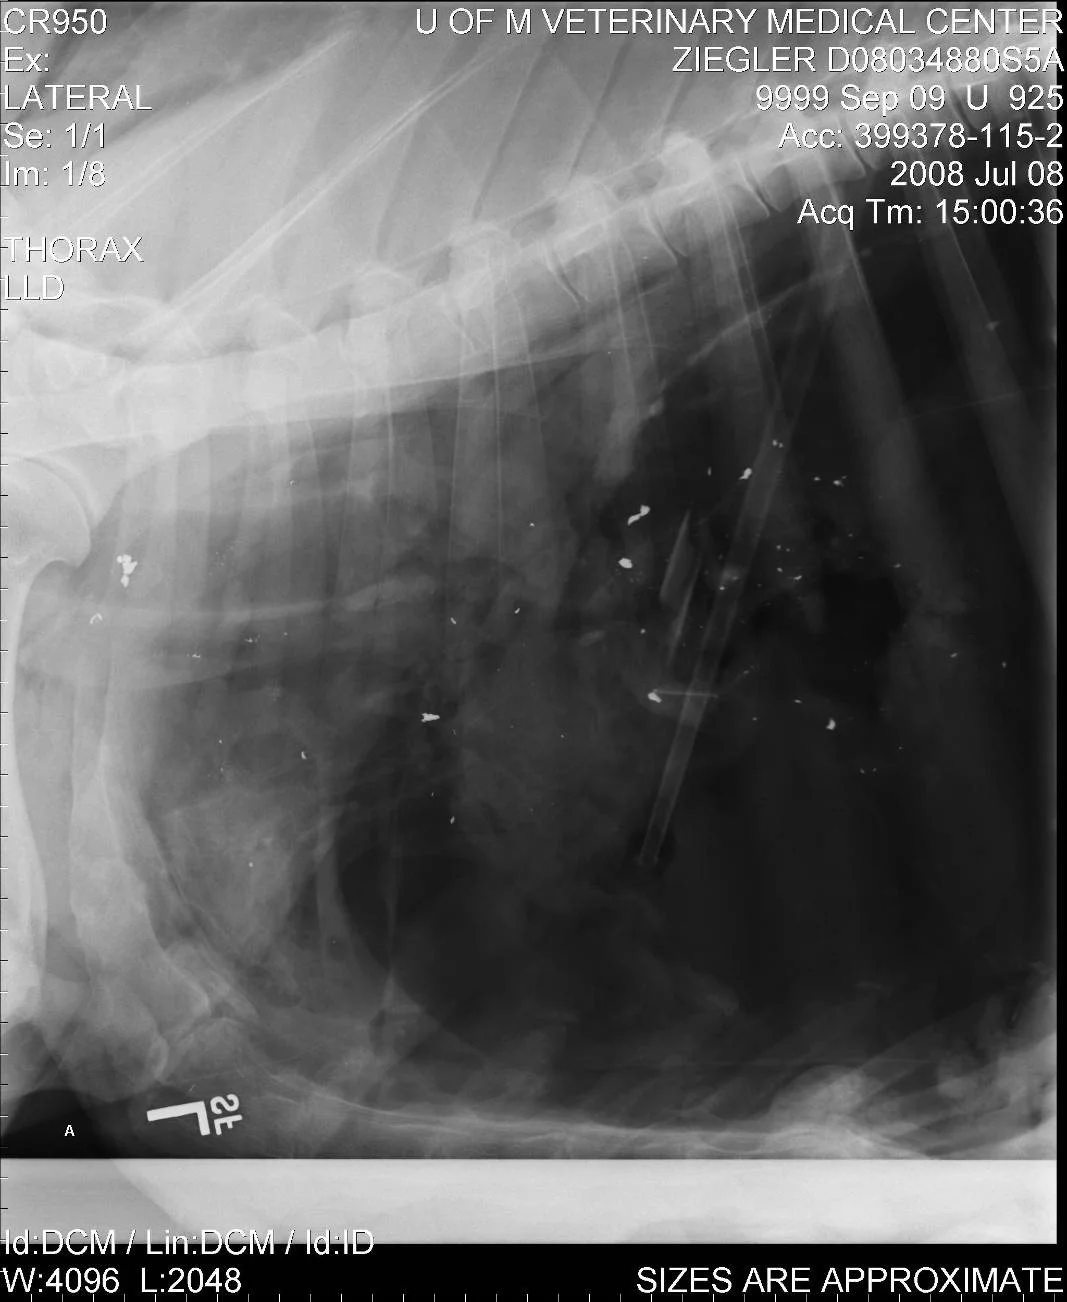

It is estimated that between 10–20% of gamebirds are wounded and unretrieved and can have embedded lead pellets in their body.

Wounded birds become easier prey for eagles and other raptors. As a raptor consumes their prey, they can unintentionally eat the lead embedded in the wounded gamebird.